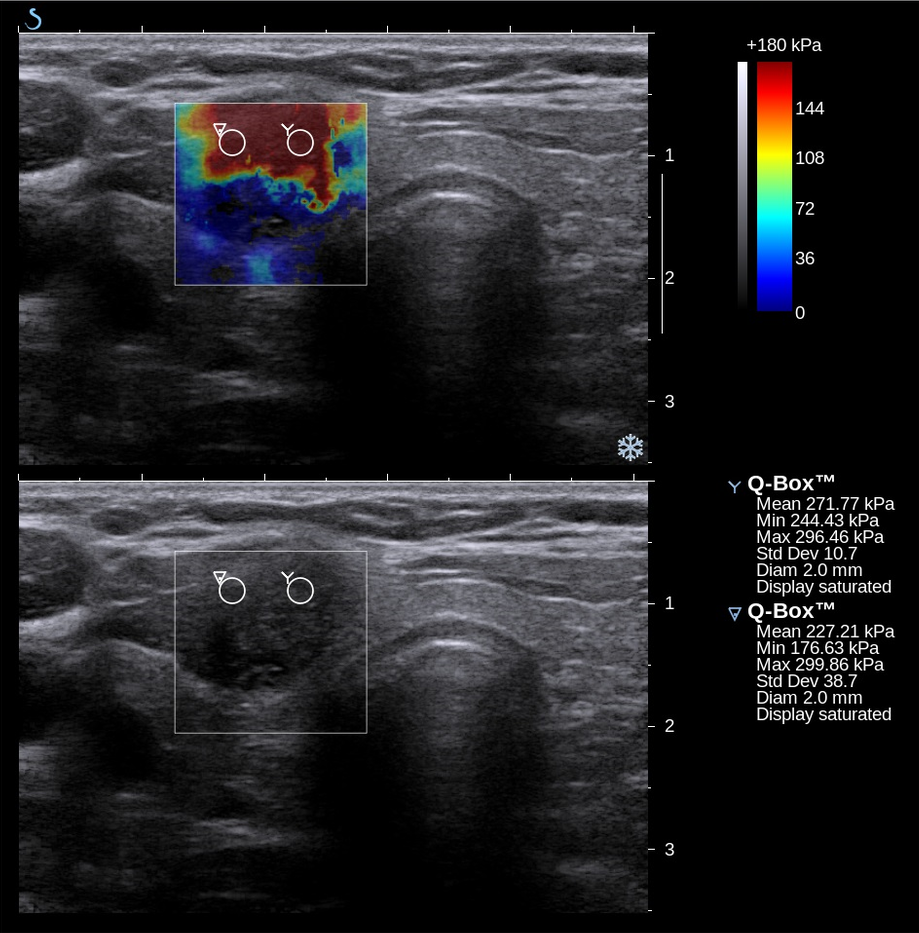

오늘날, 의료 영상 방식인 탄성영상술은 조직의 강성을 결정하는 데에도 사용될 수 있다. 수동 촉진에는 몇 가지 중요한 제한 사항이 있다. 즉, 의사의 손이 닿는 조직으로 제한되고, 개입하는 조직에 의해 왜곡되며, 질적이지만 양적이지 않다. 탄성영상술은 이러한 많은 문제를 극복하고 촉진의 이점을 개선할 수 있다.

탄성영상술은 비교적 새로운 기술로, 지난 10년 동안 주로 임상에 도입되었다. 가장 두드러진 기술은 의료 초음파 또는 자기 공명 영상 (MRI)을 사용하여 강성 지도와 비교할 해부학적 이미지를 모두 만든다.

오늘날, 의료 영상 방식인 탄성영상술은 조직의 강성을 결정하는 데에도 사용될 수 있다. 수동 촉진에는 몇 가지 중요한 제한 사항이 있는데, 의사의 손이 닿는 조직으로 제한되고, 개입하는 조직에 의해 왜곡되며, 질적이지만 양적이지 않다는 것이다. 탄성영상술은 이러한 많은 문제를 극복하고 촉진의 이점을 개선할 수 있다.

탄성영상술은 비교적 새로운 기술로, 지난 10년 동안 주로 임상에 도입되었다. 가장 두드러진 기술은 의료 초음파 또는 자기 공명 영상(MRI)을 사용하여 강성 지도와 비교할 해부학적 이미지를 모두 만든다.